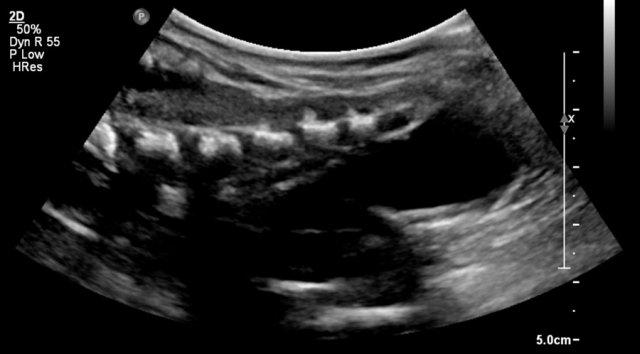

Bé trai 4 tháng tuổi với một khối lớn trong ổ bụng. Siêu âm cho thấy hỗn hợp thành phần đặc và dạng nang. Khối u tách biệt với các tạng đặc trong ổ bụng.

MRI cho thấy khối u có thành phần vừa dạng nang vừa đặc. Trong phẫu thuật, một u quái lành tính của thành dạ dày đã được cắt bỏ.